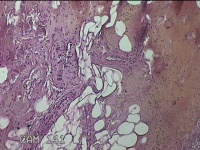

左侧会阴部皮下结节

性别

女

年龄

45岁

临床诊断

皮下结节

一般病史

发现左侧会阴部皮下结节2年余,伴近日局部隐痛不适。

标本名称

大体所见

灰白暗红色结节0.8x0.7x0.3cm一个,表面糜烂。

图1